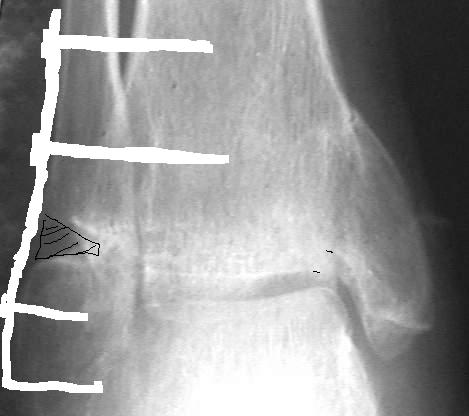

Провели костную аутопластику дефекта, металлоостеосинтез наружной лодыжки Г-образной пластиной и 4 винтами. Снимок 1, Снимок 2.

При проведении винтов выше перелома выявлен остеопороз. Есть опасность, что винты не удержат пластину при ранних нагрузках, поэтому провели винты через межберцовый синдесмоз.

Большинством мнений врачей в нашем отделении решено не проводить вмешательства на внутренней лодыжке.

Решено проводить иммобилизацию гипсовой лонгетной повязкой только в ближайшем послеоперационном периоде, разрешить ограниченную нагрузку весом тела (2 нед.). В последующем будем рекомендовать увеличивать нагрузку, проводить разработку в суставе.